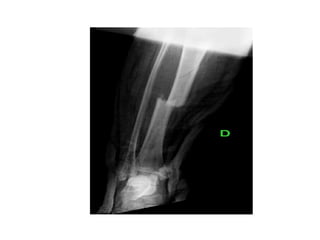

• Radiografías : examen de diagnóstico que utiliza

rayos invisibles de energía electromagnética para

producir imágenes de los tejidos internos, los

huesos y los órganos en una placa